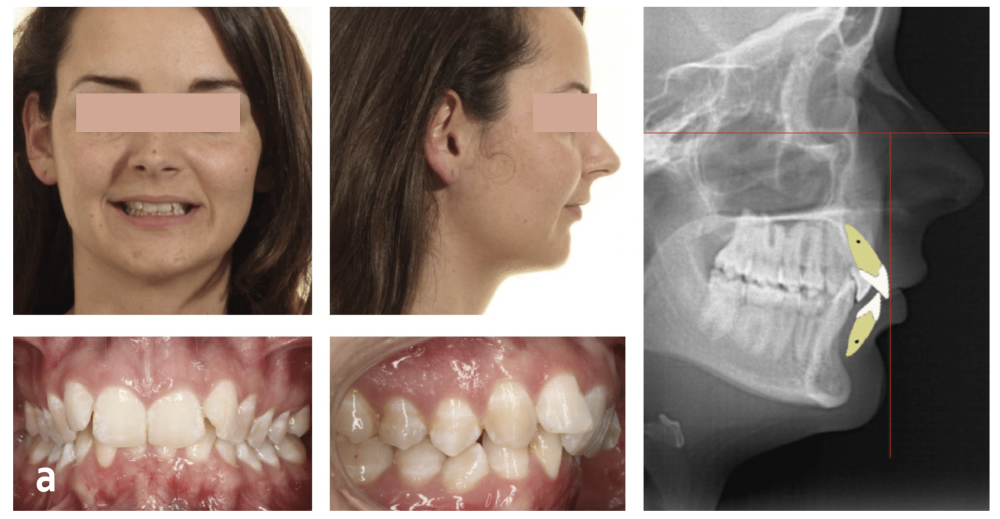

La céphalométrie aide au diagnostic. De manière simplifiée, sur une téléradiographie de profil, le plan de Francfort puis le plan antérieur de Cocconi, qui passe par le point le plus antérieur de l’os maxillaire, sont tracés ; la ligne qui passe par la face vestibulaire de l’incisive centrale maxillaire doit être tangente à ce plan (fig. 1). L’incisive centrale mandibulaire doit être au contact de son antagoniste. Si, à la suite de la simulation de cette analyse, l’incisive du bas est en dehors de l’enveloppe osseuse, cela implique le choix thérapeutique d’une chirurgie orthognatique du maxillaire et/ou de la mandibule (fig. 2).